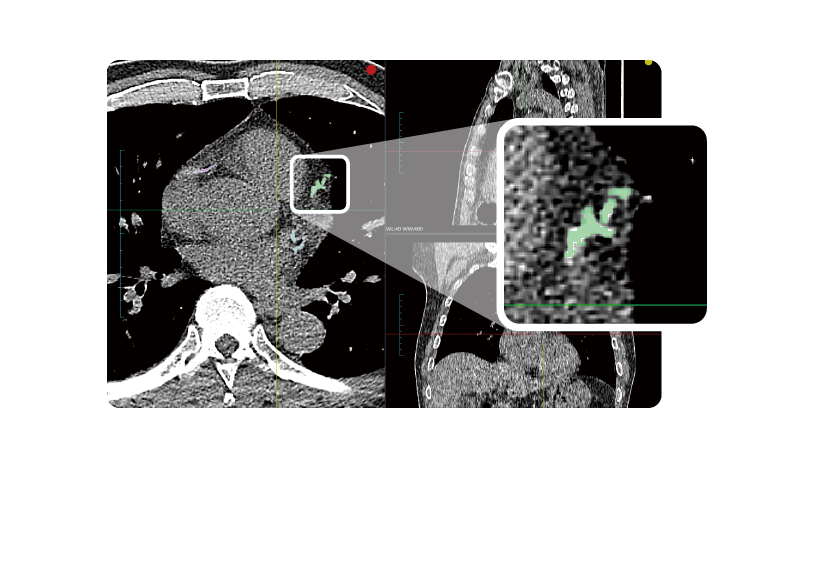

用於分析肺部CT影像並自動偵測結節

Ti-LUNG軟體是一款肺部電腦斷層決策支援系統,用於檢視、分析肺部電腦斷層影像,識別疑似結節區域和評估其良、惡性程度,提供肺部結結特徵和Lung-RADS分級,以提升醫師閱片效率,並快速產生符合臨床需求的診斷報告,增加工作效率。